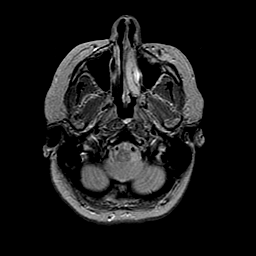

MR Study #2 -- Slice #9

[Home][Help][Clinical][Tour 1][Tour 2][Tour 3] Slice 9